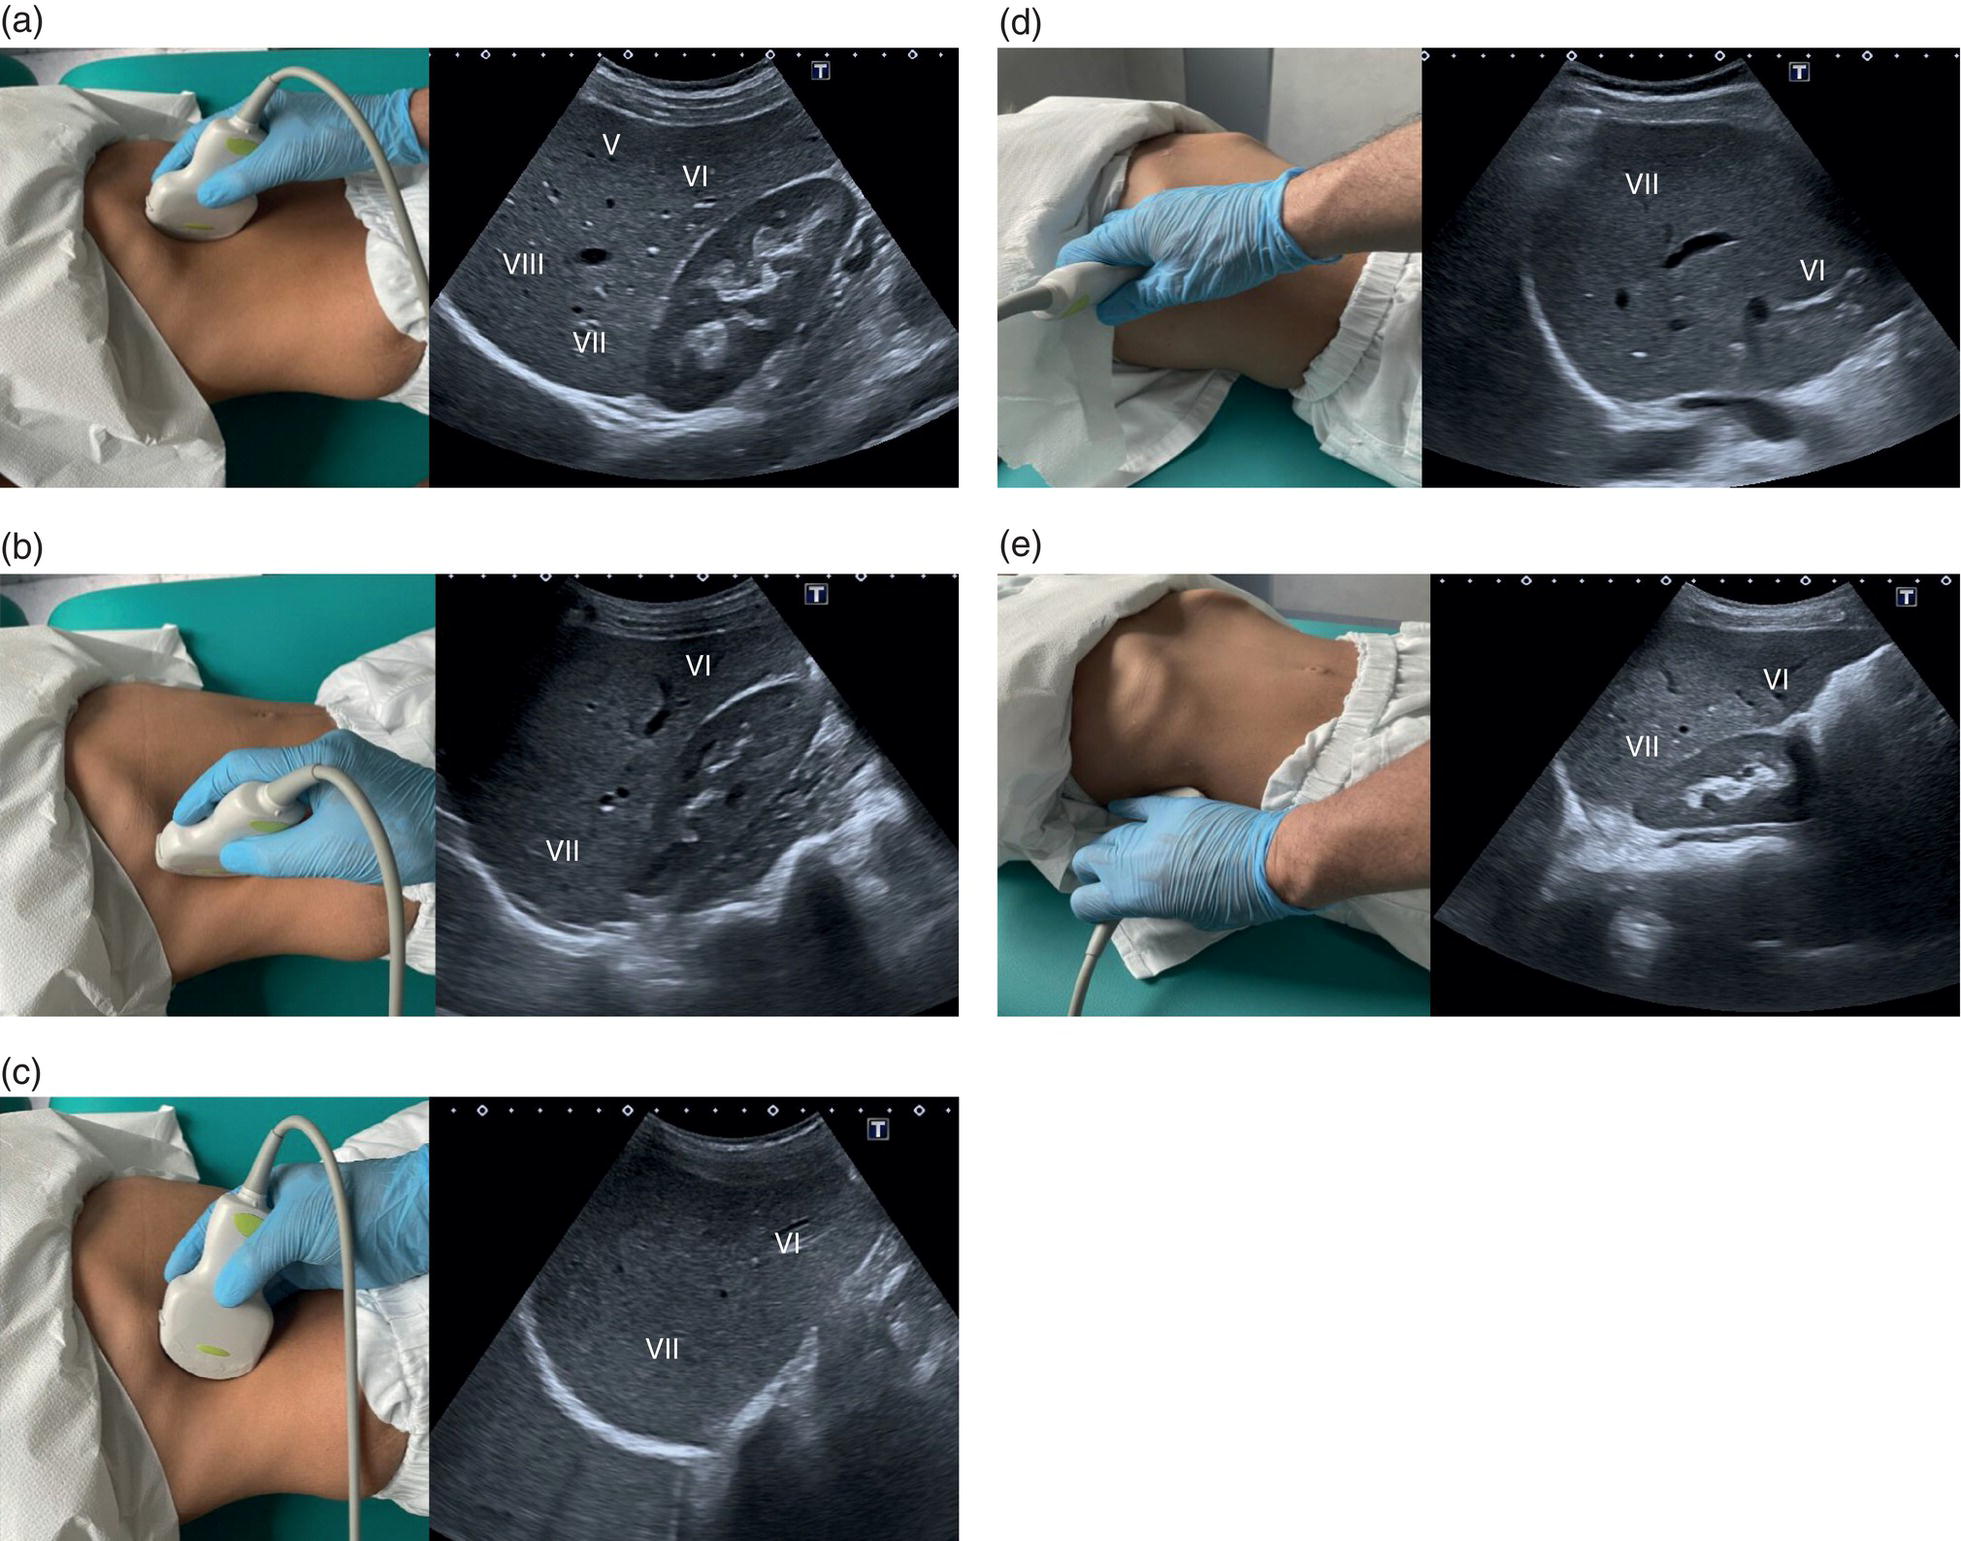

The right liver lobe includes segments V–VIII, which should be assessed in both the LS and TS planes via a subcostal and intercostal approach, as shown in Figures 3.24–3.26 (Video 3.5). Start again by keeping the probe in the epigastric region in a TS view. By angling upwards, you will visualise the most cranial liver segments (from left to right of the patient will be segment II, IV, VIII) and you will image part of the heart, eventually excluding or highlighting the presence of a pericardial effusion. Then, remaining in the subcostal scanning position, turn the probe oblique (rotating anticlockwise) and slowly angle downwards, making small adjustments as required. By doing so you will visualise the confluence of the three hepatic veins and the IVC from two slightly different angles, with the oblique scan favouring the visualisation of the right hepatic vein (Figure 3.24) (Video 3.5). Maintaining the same probe position and slowly moving downwards, you will visualise first the GB and left branch of the PV and then, eventually turning the patient left side down and making small adjustments, you will visualise the PV crossing and ‘dividing’ the liver in a cranial and caudal region (Figure 3.25) (Videos 3.6 and 3.7). Bear in mind that according to body habitus, when sweeping downwards the PV might appear before the GB or viceversa. Representative images of the right lobe should also be obtained intercostally, moving the probe from one intercostal space to another angling upwards and downwards in order to have a complete view from each angle (Video 3.5). A representative image of the liver with the right kidney is important to allow comparison of its echogenicity to the cortex of the right kidney to diagnose or exclude steatosis. This image can be obtained in the LS plane, starting along the mid‐clavicular line and sweeping outwards (laterally) until the kidney is visualised, or intercostally in case of bowel gas interference (Figure 3.26) (Video 3.8).

Based on the divisions of the portal and hepatic veins, the liver may be divided into eight segments, as first suggested by the French surgeon Claude Couinaud in 1957 (Figure 3.14) [4]. This classification relies on the fact that each of these segments has its own individual blood supply and might be resected without jeopardising the viability of other segments. In this classification, the liver segments II and III are situated to the left of the LHV and falciform ligament, and the left branch of the PV (LPV) divides them into segment II (above the PV) and segment III (below the LPV). Segment IV is situated between the LHV and the MHV and the LPV divides them into segment IVA (above the LPV) and segment IVB (below the LPV). Segments V and VIII are located between the MHV and RHV, whereas segments VI and VII represent most lateral segments situated to the right of the RHV. The right branch of the RPV divides segment V (caudal) from VIII (cranial) and segment VI (caudal) from VII (cranial) (Figure 3.15). On the dorsal, central part of the liver, between the IVC and the venous ligament, lies the caudate lobe that corresponds to segment I (Figures 3.6 and 3.12c).